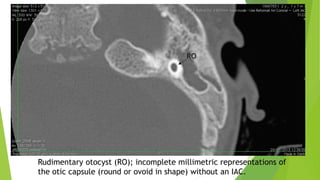

A rudimentary otocyst is used to define incomplete milimetric representations of

the otic capsule (round or ovoid in shape) without an IAC. Parts of the SCCs may

accompany rudimentary otocyst.

This pathology represents an anomaly between a Michel deformity and common

cavity (CC).

In Michel deformity, there is no inner ear development, while in CC, there is an

ovoid or round cystic space instead of a separate cochlea and vestibule.

The CC communicates with the brainstem via the nerves in the IAC. The

rudimentary otocyst is a few millimeters in size without the formation of an IAC.

Rudimentary otocyst (RO); incomplete millimetric representations of

the otic capsule (round or ovoid in shape) without an IAC.